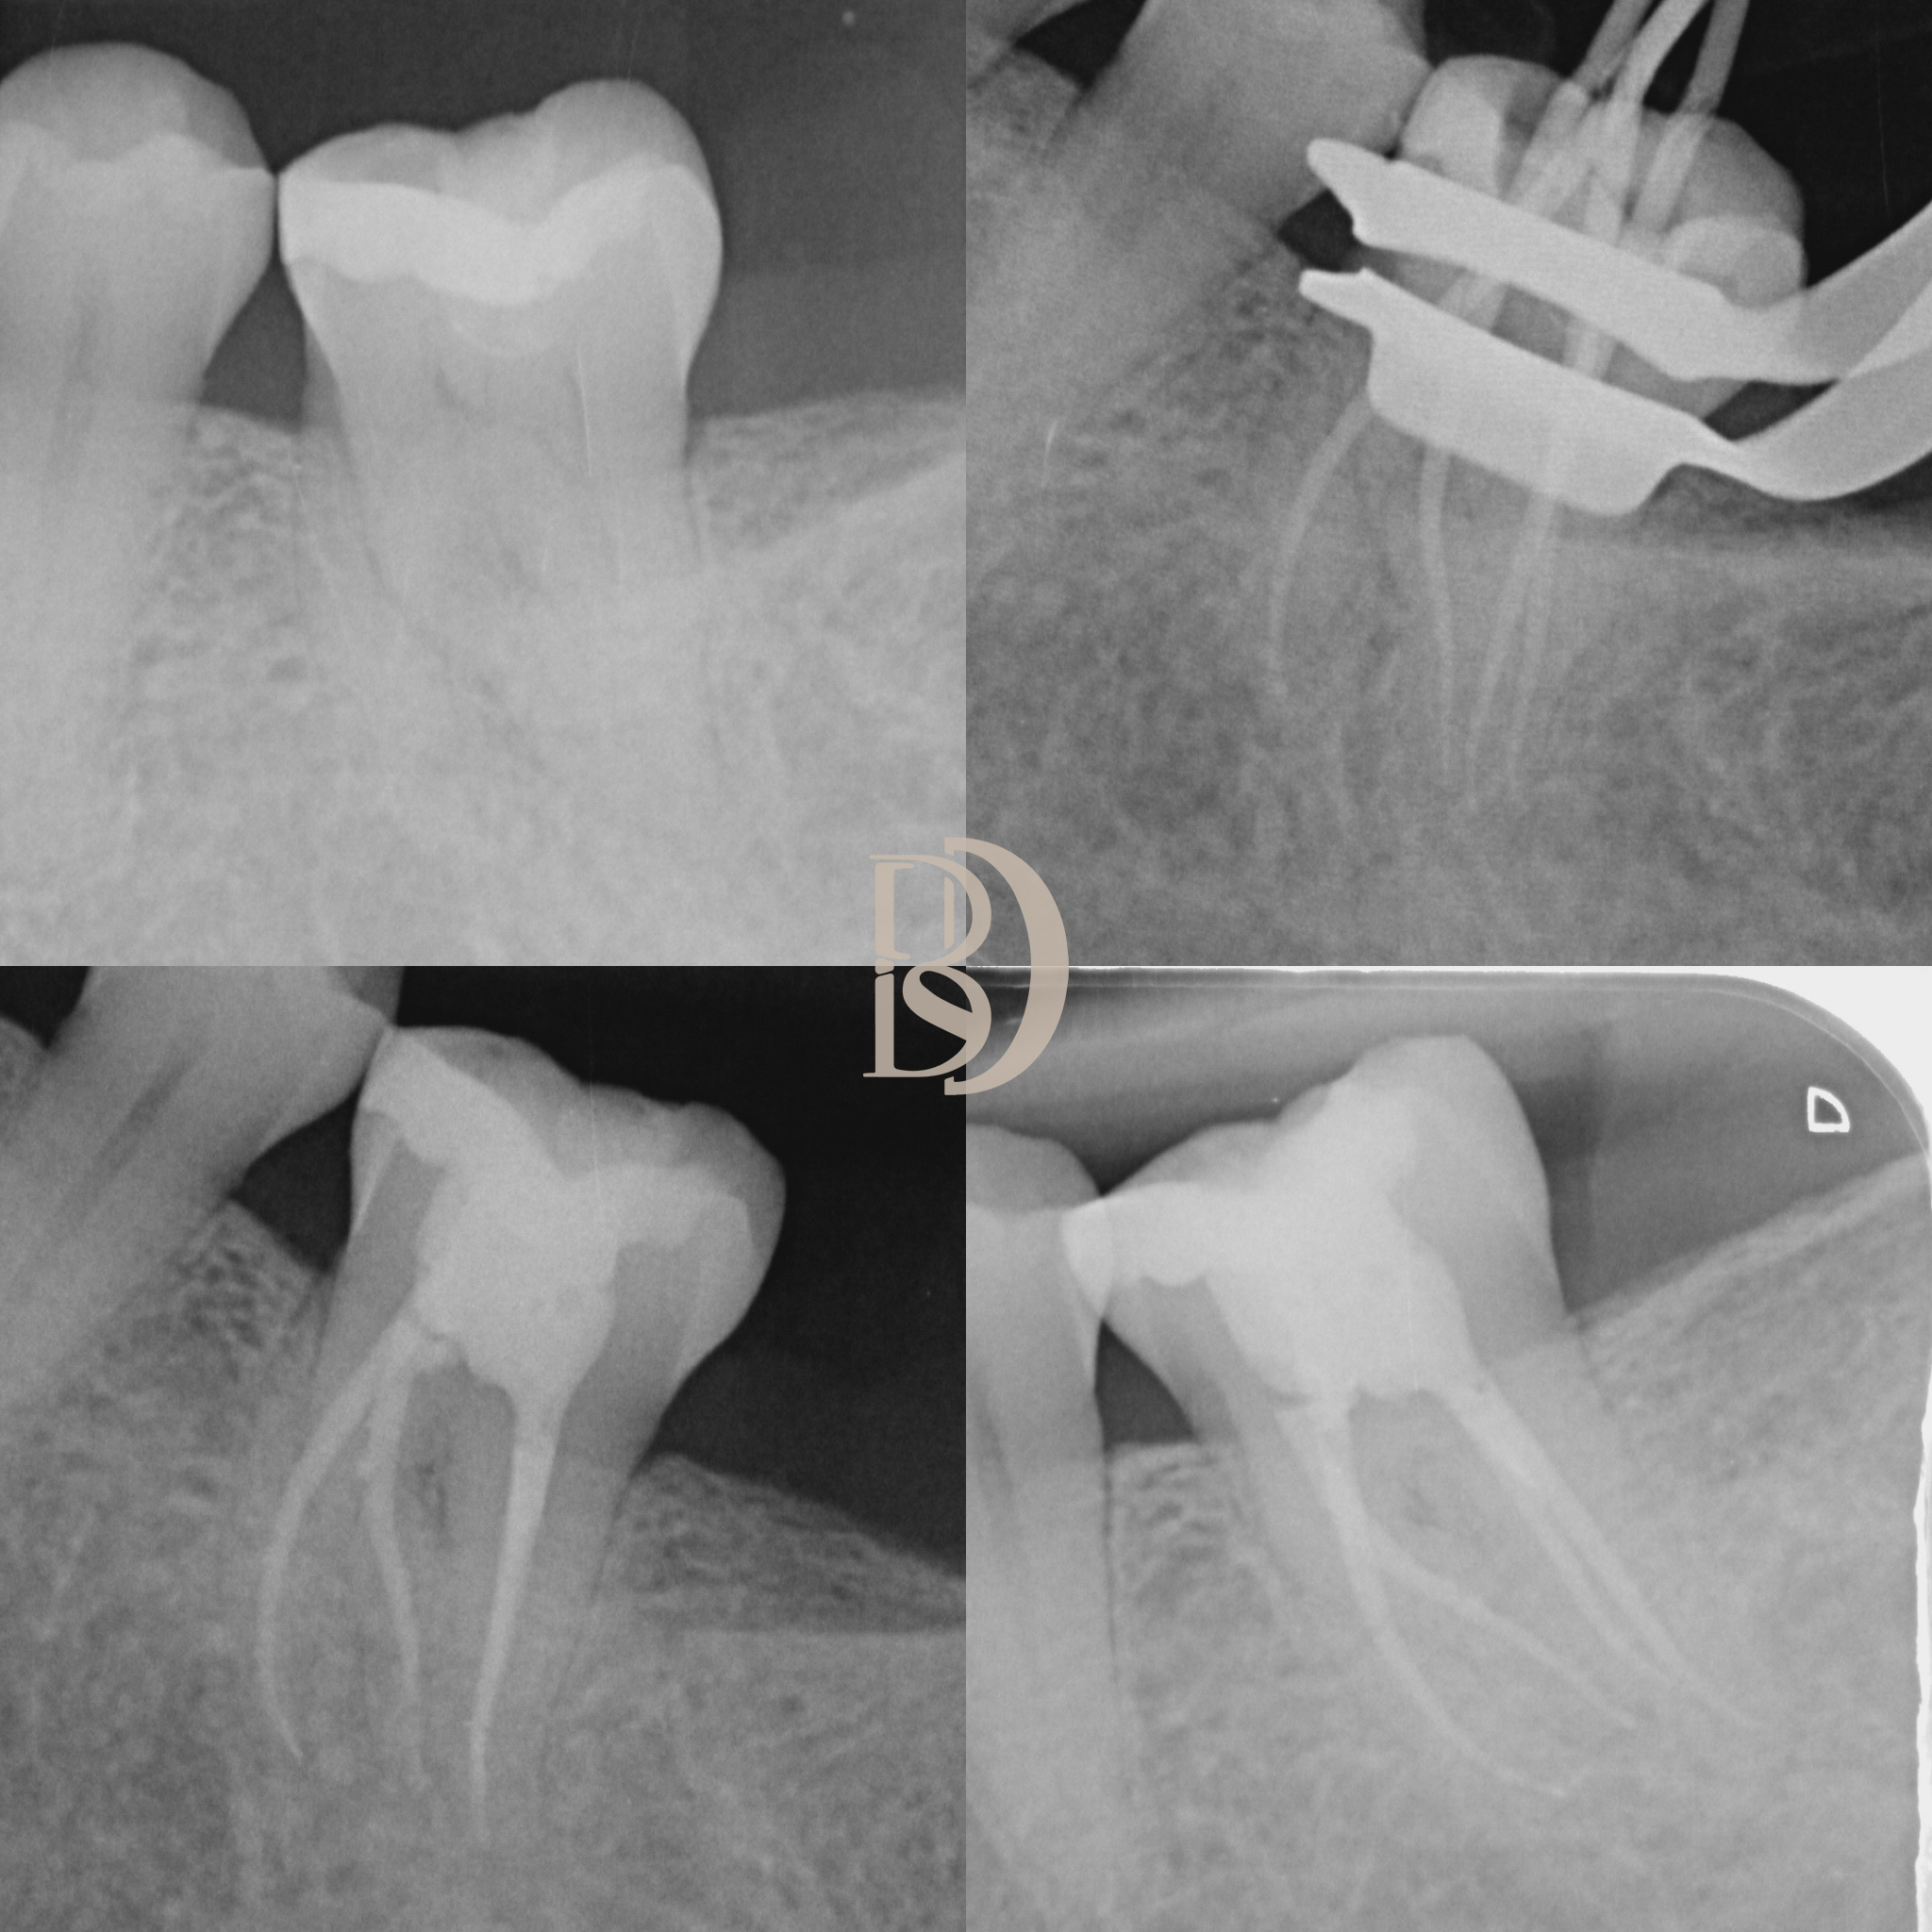

Some examples of Dr Fred’s Endodontic cases:

Dental X-ray showing multiple teeth, including root canal treatment on molars.

Dental X-rays displaying teeth and root canals